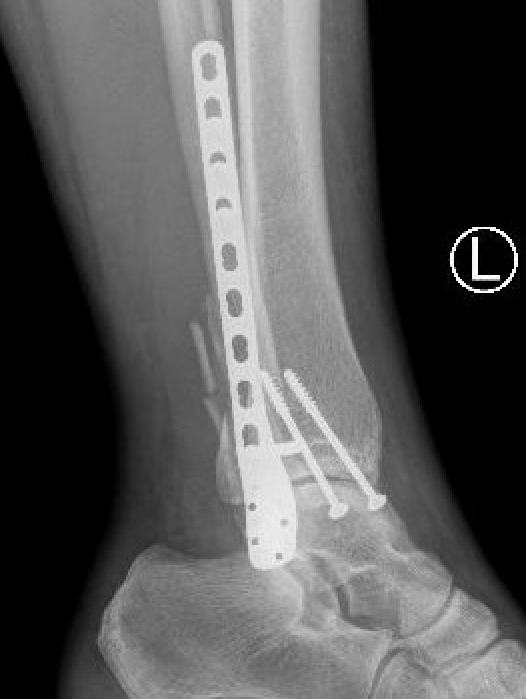

Bimalleolar fractures

Medial malleolus + Weber B lateral malleolus

1. Interfragmentary lag screw + neutralisation plate

2. Locking plate |

2 partially threaded lag screws Tension band wire Plate |

Should be stable with Weber B Cotton test Clamp on fibula and attempt to open syndesmosis under II) |